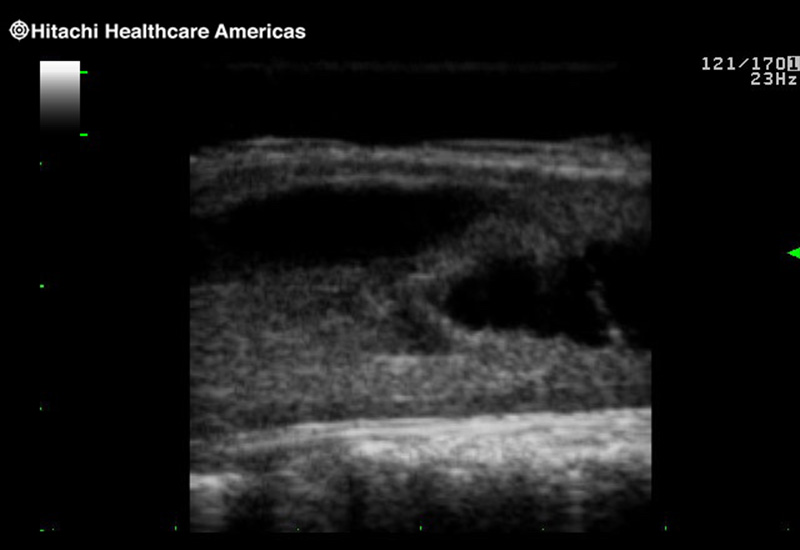

Giving the surgeon complete control

The Fujifilm Healthcare transducer utilizes the full benefits of the Wrist Articulation™ of the robotic instruments to capture real-time ultrasound imaging even at complex angles and difficult-to-reach areas.

The next level in Robotic Ultrasound

Full wrist articulation with optimized functional length.

A critical function of robotic ultrasound guidance is tumor margin identification. Fujifilm's family of robotic probes all have the optimum location of the attaching mechanism that allows for full wrist articulation of the probe. The result is an increased confidence that the tumor margins have been completely identified.